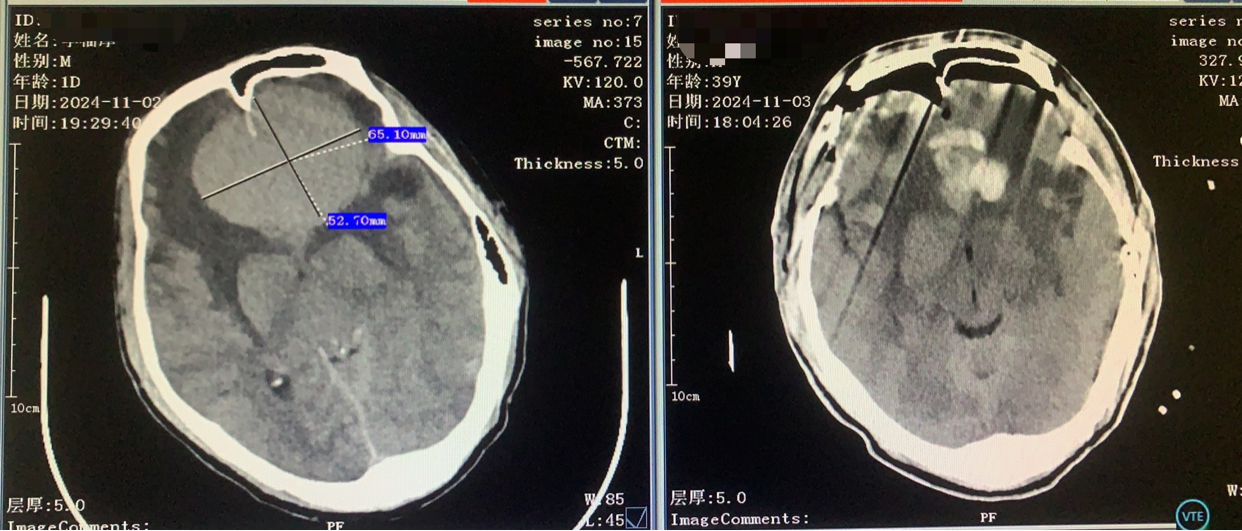

术前CT

双侧入路计划(为降低优势半球损伤风险先右侧处理,实在不好搞再左侧)

从右额分块切除处理大部分后,因条件所限单侧入路风险高遂加开左侧额外侧(骨窗较右侧小)。

术前术后对比